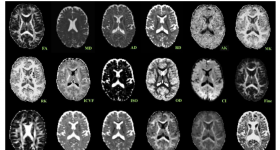

人類(lèi)大腦白質(zhì)的宏觀和微觀結(jié)構(gòu)在整個(gè)發(fā)育和衰老過(guò)程中都經(jīng)歷了實(shí)質(zhì)性的變化。當(dāng)前的研究者對(duì)這些描述整個(gè)生...